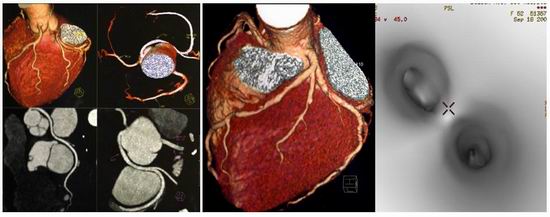

名称:高端CT Aquilion One TSX-301A

主要功能Aquilion One是东芝新型0.35秒/320层/360度动态容积扫描CT,采用Volumexact+算法、TCOT算法、新型重建模块,为临床提供任何方向更清晰准确的三维图像。特别适合外伤一站式检查、神经系统和心脏的检查的快速检查要求,可以得到纯动脉和纯静脉成像。揭开了新的应用领域,尤其在动态容积成像和运动系统成像。